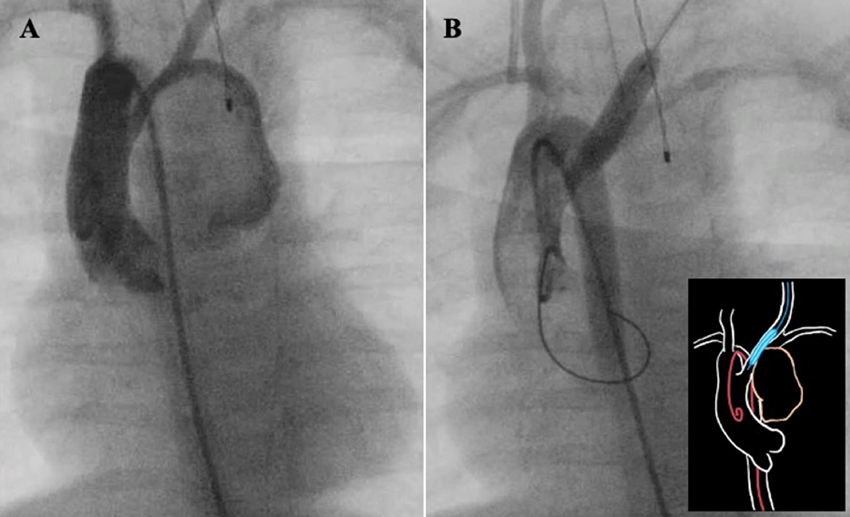

Pediatric Cardiology and Cardiac Surgery 38(4): 243-248 (2022)

Fig. 3 Angiogram taken before the surgery

A: Aortography image taken before balloon occlusion of the aneurysm. A 4Fr sheath was placed in the right femoral artery, and aortography was performed using a pigtail catheter. The aneurysm was depicted, and the inflow vessel of the aneurysm was confirmed. B: Aortography after balloon occlusion of the aneurysm By the cut-down method, a 4Fr sheath was placed in the left common carotid artery; a Sterling™ Balloon Dilatation Catheter 6 mm (Boston Scientific Japan) was inserted, and balloon dilation was performed at the opening of the aneurysm. Balloon dilation performed again with a pigtail catheter confirmed a lack of aneurysms.